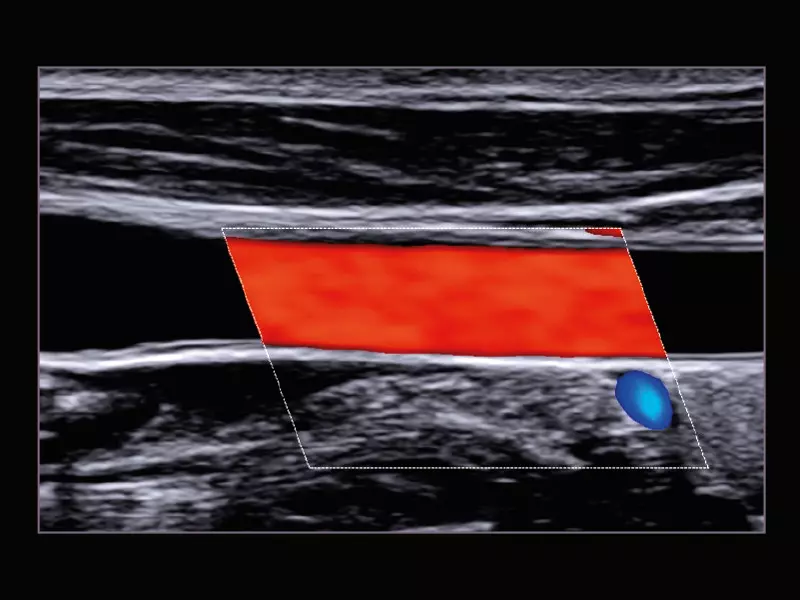

Q7 - Carotid

Q7 - Carotid